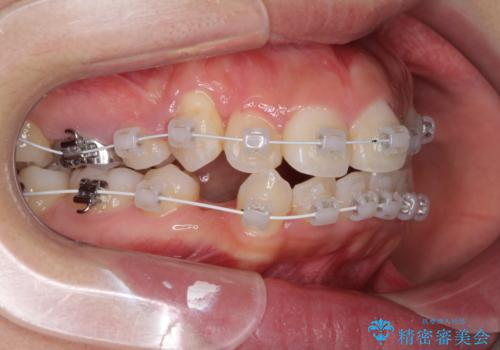

- 矯正装置

- 審美装置

咬み合わせの乱れが著しく、治療途中で一部反対咬合となってしまいました。

アンカーなどをうまく使用して、3年の期間を要してきれいに仕上げることができました。